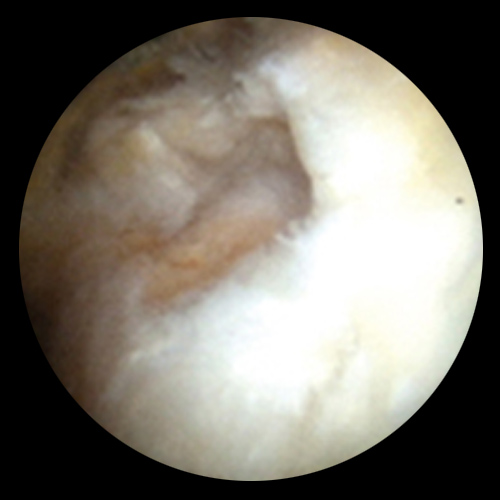

관절내시경은 작은 절개를 통해 초소형 카메라와 특수 기구를 관절 내부에 삽입하여 손상 부위를 직접 확인하고 치료하는 방법입니다.

어깨, 무릎, 발목 등 다양한 관절에 적용되며, 진단과 치료를 동시에 시행할 수 있는 최소침습 수술입니다.